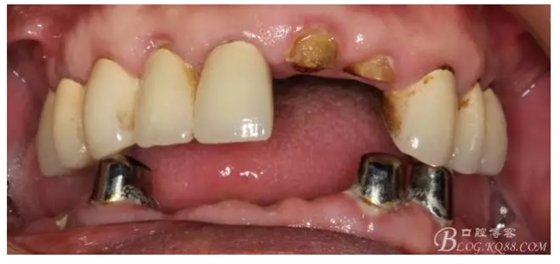

還要有足夠的牙本質(zhì)肩領(lǐng),大家現(xiàn)在可以看到患者的下頜套筒冠還是非常好的

修復(fù)后照片,

患者的口腔衛(wèi)生保持的不好,有大量的軟垢附著,

最近復(fù)查的照片,牙周維護(hù)好一些了,畢竟是一個(gè)80歲的老爺爺了,每次來(lái)拄著拐,還要跟著很多人攙扶著過(guò)來(lái)很不容易了。